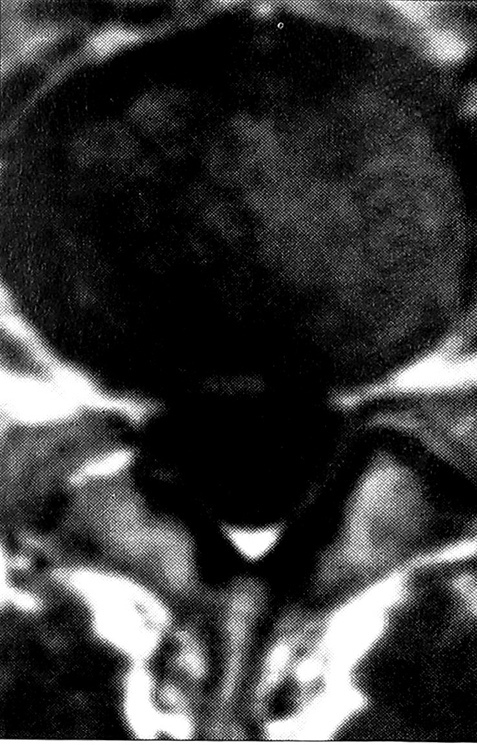

Большинство наших больных поступили с запущенным процессом, длительно леченным консервативно. При магнитно-резонансной томографии выявлены следующие виды поражения диска: протрузия — у 215 больных, экструзия — у 380, секвестрация — у 122 (в том числе внутриканальный секвестр — у 118, внутриоболочечный — у 4). В 96,3% случаев мы обнаружили или значительное выпячивание межпозвонкового диска, вызывающее грубую компрессию корешка, или секвестр (рис. 1), причем у большинства пациентов этот процесс существовал длительное время. Только у 3,7% больных корешковый синдром был вызван небольшой протрузией диска (рис. 2), «подходящей» для применения эндоскопической технологии. У 226 (31,5%) больных имелась сочетанная патология: у 116 — стеноз позвоночного канала (гипертрофия задней продольной, желтых связок), у 38 — спондилолистез I—II степени, у 72 — спаечный процесс (у 49 —вокруг одного корешка, у 19 — внутриканальный, у 4 — внутриоболочечный).

Рис. 2. Небольшая протрузия диска L4-5 (магнитно-резонансная томограмма).